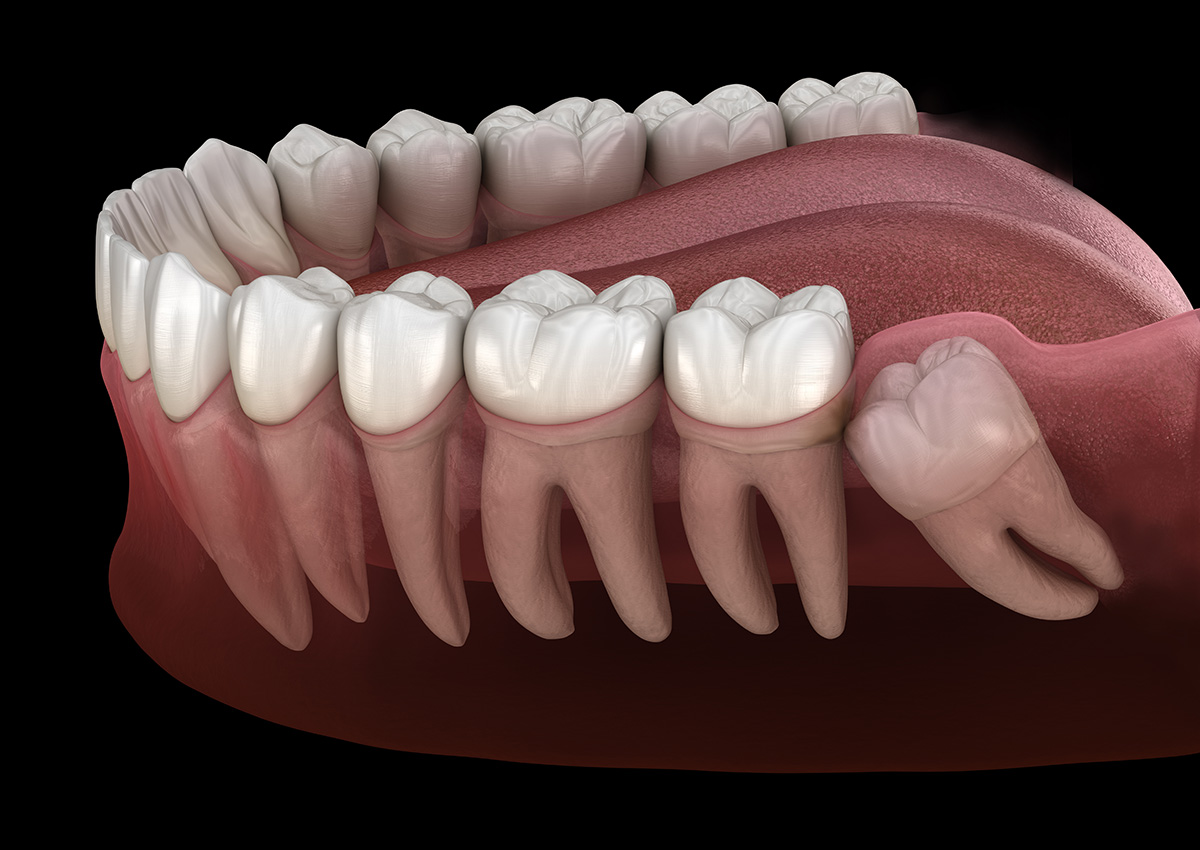

The most common reason for wisdom teeth extractions is insufficient space in the mouth. When there is not enough room for the wisdom teeth to emerge properly, they may become impacted, meaning they cannot fully break through the gum line. Impacted wisdom teeth can lead to various issues, including pain, infection, and damage to neighboring teeth.

Wisdom teeth may erupt at awkward angles or positions, causing them to press against neighboring teeth. This misalignment can result in crowding and disrupt the alignment of your existing teeth.